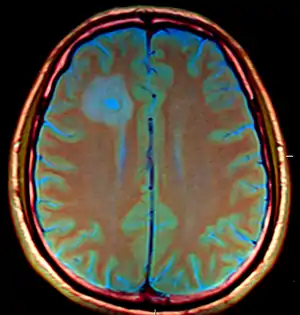

Brain abscess in a person with a CSF shunt.[1] | |

- MRI (T1 with contrast) showing the ring-enhancing lesion. From a rare case report of an abscess formed as a complication of the CSF shunt. Jamjoom et al., 2009.[1]

The diagnosis is established by a computed tomography (CT) (with contrast) examination. At the initial phase of the inflammation (which is referred to as cerebritis), the immature lesion does not have a capsule and it may be difficult to distinguish it from other space-occupying lesions or infarcts of the brain. Within 4–5 days the inflammation and the concomitant dead brain tissue are surrounded with a capsule, which gives the lesion the famous ring-enhancing lesion appearance on CT examination with contrast (since intravenously applied contrast material can not pass through the capsule, it is collected around the lesion and looks as a ring surrounding the relatively dark lesion). Lumbar puncture procedure, which is performed in many infectious disorders of the central nervous system is contraindicated in this condition (as it is in all space-occupying lesions of the brain) because removing a certain portion of the cerebrospinal fluid may alter the concrete intracranial pressure balances and causes the brain tissue to move across structures within the skull (brain herniation).

Ring enhancement may also be observed in cerebral hemorrhages (bleeding) and some brain tumors. However, in the presence of the rapidly progressive course with fever, focal neurologic findings (hemiparesis, aphasia etc.) and signs of increased intracranial pressure, the most likely diagnosis should be the brain abscess.